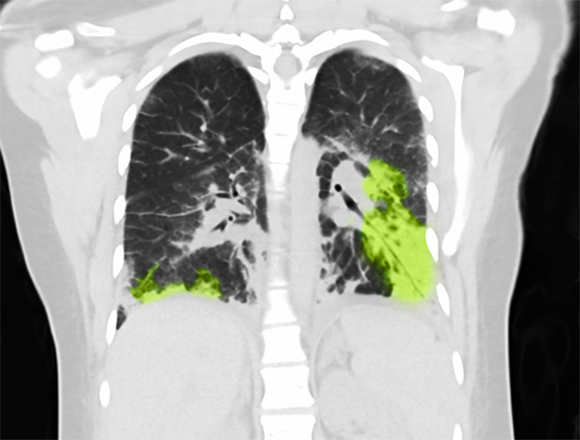

في عام 2019، كان هناك ازدياد حادّ في عدد حالات العلاج في المستشفيات في الولايات المتّحدة بسبب استخدام السجائر الإلكترونيّة. صورة أشعّة سينيّة لفتاة تبلغ من العمر 19 عامًا أصيبت بأضرار جرّاء تدخين السجائر الإلكترونيّة | المصدر: Steven Needell / Science Photo Library

نظرًا للوقت القصير نسبيًّا والّذي مرّ منذ تطوير السيجارة الإلكترونيّة، والّذي لا يُتيح تحديد أضرارها طويلة المدى، لذلك، فإنّ الدراسات الّتي تبحث في عواقبها الصحيّة لا تقدّم إجابات شاملة. على سبيل المثال، فقط حتّى عام 2019، قام مركز السيطرة على الأمراض والوقاية منها (CDC) بتحديد متلازمة جديدة تُسمّى "الأمراض الرئويّة المرافقة للتدخين الإلكترونيّ أو منتجات التبخير (Vaping)"، أو EVALI باختصار، وذلك بعد زيادة حادّة في عدد حالات دخول المستشفى بسبب استخدام السجائر الإلكترونيّة. تشمل هذه المتلازمة أعراضًا كضيق في التنفّس، ألم في الصدر، ارتفاع في درجة الحرارة، نبض سريع، سعال، آلام في البطن وقيء. في غضون عام واحد، تمّ تسجيل 2800 حالة علاج في المستشفى بسبب متلازمة EVALI، وانتهت 68 منها بالوفاة. من المحتمل أن تكون معظم حالات التقييم هذه ناتجة عن استهلاك فيتامين E أسيتات في سائل التبخير.